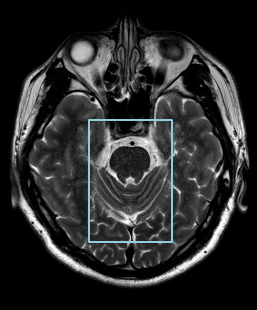

PIQE for MR

极速高分辨率成像

在磁共振领域,深度学习技术对图像进行降噪、上采样、减轻振铃伪影的处理,带来了清晰且细节丰富的图像。

过去,高分辨率图像的获取往往伴随着漫长的扫描时间,这影响了图像获取的效率,对于危重疾病的快速诊断是一大挑战。然而,PIQE技术的出现彻底颠覆了这一局面。此次发布的全新3T磁共振Galan Supreme,搭载全新的自研磁体和梯度线圈,并深度融合PIQE技术,可以实现在不增加扫描时间的前提下,轻松获取到高分辨率的图像,为临床带来了兼具高效与高质量的影像体验。

左右滑动查看更多